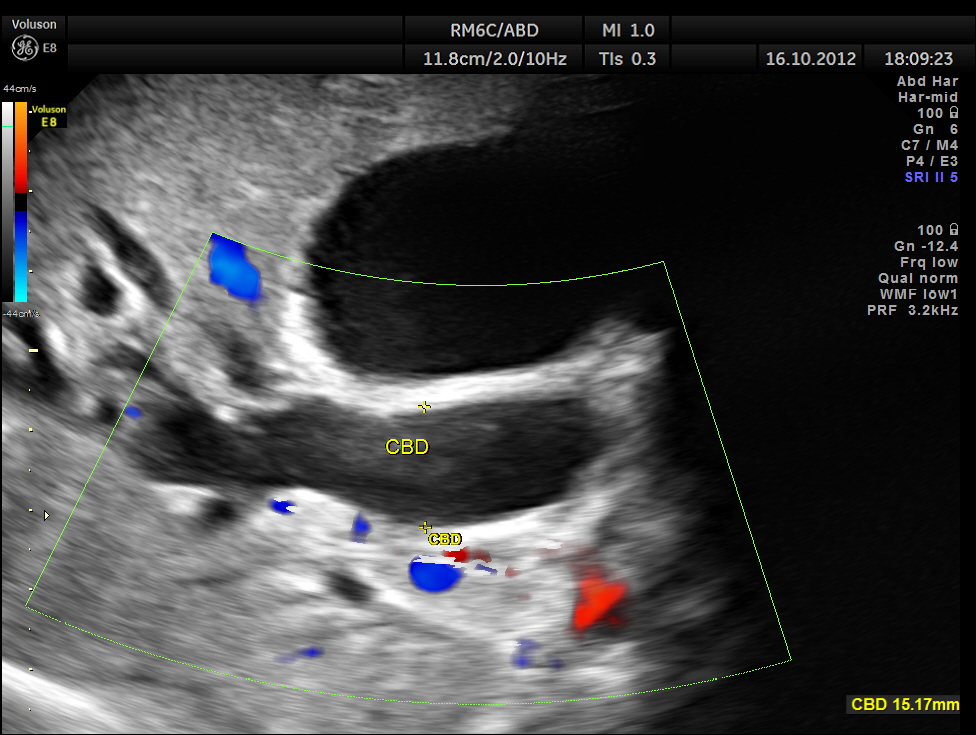

Courvoisier’s law (or Courvoisier syndrome, or Courvoisier’s sign or Courvoisier-Terrier’s sign) states that in the presence of an enlarged gallbladder which is nontender and accompanied with mild jaundice, the cause is unlikely to be gallstones. Usually, the term is used to describe the physical examination finding of the right-upper quadrant of the abdomen. This sign implicated possible malignancy of the gall bladder or pancreas and the swelling is unlikely due to gallstones.

This was a 55 year old man with history of jaundice and upper abdominal pain .